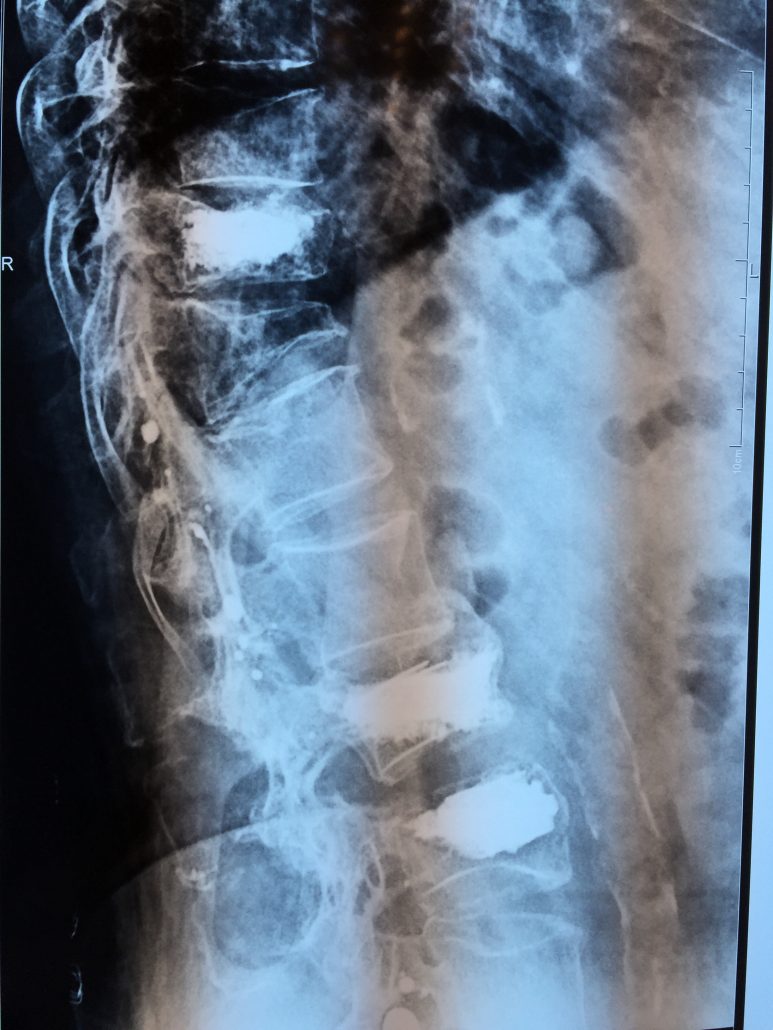

El sistema SpineJack® ha sido diseñado para la reducción anatómica de Fracturas Vertebrales por Compresión (FVC de tipo A1, A2 y A3 según la clasificación de Magerl), con o sin patologías subyacentes que afecten a la calidad del hueso, como la osteoporosis y las lesiones de origen oncológico (metástasis osteolítica o mieloma).

Diversos estudios clínicos y epidemiológicos han demostrado que existe correlación entre la deformación vertebral y problemas clínicos como la cifosis postraumática, que ha sido descrita como una de las deformidades postraumáticas potencialmente más graves. En este contexto, Vexim ha diseñado el implante SpineJack® para ofrecer al médico una solución totalmente controlada y completa para el tratamiento de las FVC, que permite primero una reducción anatómica y después una estabilización segura.